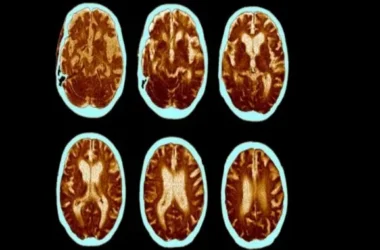

دراسة جديدة تكشف ارتباطًا مفاجئًا بين خلايا المناعة ومرض ألزهايمر

اكتشفت دراسة حديثة أن نوعًا معينًا من الخلايا المناعية، وهي الخلايا التائية CD8، قد يكون له دور حاسم في تطور مرض ألزهايمر. اكتشف التفاصيل الكاملة لهذا البحث الواعد.